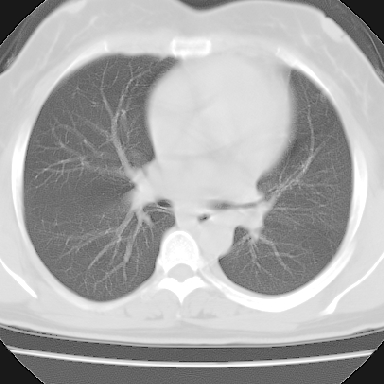

左下肺肿块影,内可以见小泡征,并见厚壁空洞形成,洞内缘凹凸不平,可见壁结节。靠近胸膜侧可见胸膜凹陷征。左侧胸腔内可见少量低密度积液影。右肺可见两处高致密的小结节影。

考虑:左下肺周围型肺癌伴右肺转移

左下肺肿块影,内可以见小泡征,并见厚壁空洞形成,洞内缘可见壁结节。靠近胸膜侧可见胸膜肥厚粘连。双肺可见多发性小结节影。

考虑:左下空洞性肺癌伴两肺转移

左下肺有空洞,壁厚薄不均,壁结节,两肺多发小结节影,腋窝下可疑淋巴结肿大,综上所述考虑周围性肺癌并两肺转移可能性大,建议穿刺活检。

支持癌性空洞:壁厚,无液平,内壁不规则,外壁呈分叶状,较大,偏心性,壁结节,胸膜凹陷,转移灶。